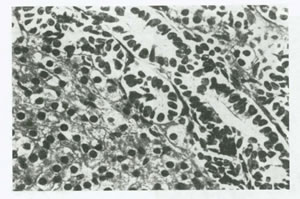

كارسينوم لوله فالوپ، معمولاً توسط تورم ها به علت رشد داخل مجرايي آن مشخص مي شود. تنها پس از باز كردن بافت لوله است كه علت عفوني را مي توان كنار گذاشت و در برش بافتي، لوله متورم بوده و با يك تومور پاپيلري يا جامد پر شده است (شكل 47). ممكن است مناطق از نكروز و خونريزي نيز ديده شود. تومور در 10 تا 26 درصد از بيماران دو طرفه است ولي علت دو طرفه بودن خوب مشخص نشده، چون بعضي معتقدند نشاندهنده يك متاستاز است و بعضي معتقد به علت چند كانوني بودن تومور هستند. قسمت عمده تومورهاي لوله فالوپ آدنوكارسينوم نوع سروز است كه از لحاظ بافت شناسي مشابه با كار سينوم سروز تخمدان مي باشد. بقيه انواع گزارش شده كه بسيار نادر مي باشند شامل: موسينوس، اندومتروئيد، سلول روشن و اسكواموس هستند. آدنوكارسينوم سروز تمايز يافته از پاپي هاي ظريف و شاخه شاخه تشكيل +1106

شده است. در حالي كه نوع كم تمايز آن حاوي صفحات توپر سلولي با نواحي نكرز است(شكل 48).

- شکل 48:کارسينوم لوله فالوپ .کارسينوم سروز لوله فالوپ ظاهر ميکروسکوپي مشابه کارسينوم اوليه تخمدان دارد.در اين مثال سلول ها به صورت پا پي هاي ظريف و آشيانه هاي مجزا طبقه بندي شده اند.